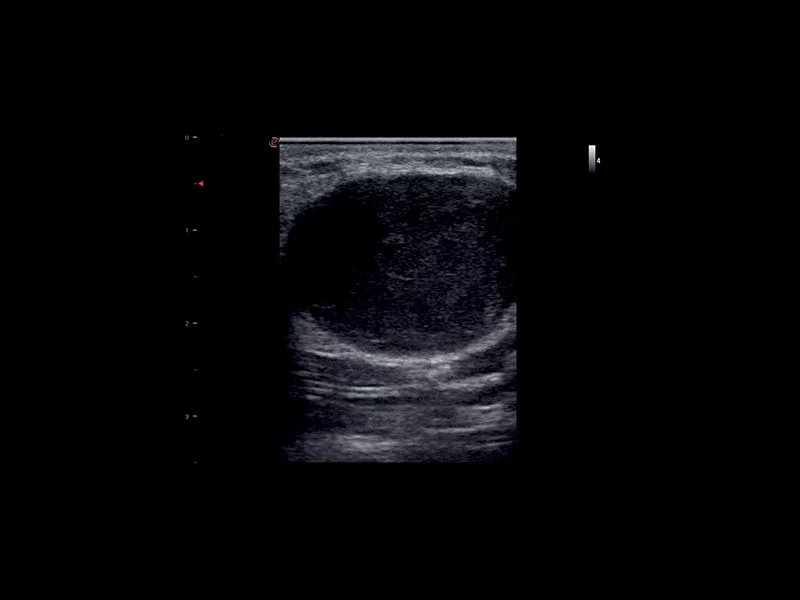

MyLab™9 Platform - High resolution imaging in testis

MyLab™9 Platform - High resolution imaging in testis